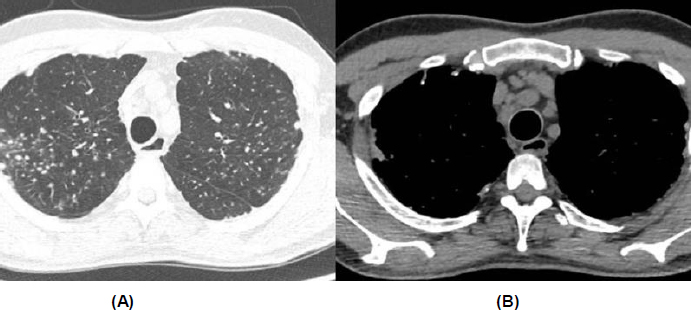

Although there were no parenchymal changes on chest computed tomography (CT), there was mediastinal lymphadenopathy and multiple pulmonary nodules, some calcified, predominantly in the upper lobes (Fig. 2). Spirometry revealed a moderate restrictive ventilatory disorder, with forced vital capacity (FVC) of 2.93 L (63%), forced expiratory volume in 1 second (FEV1) of 2.35 L (62%), and the ratio of FEV1 to FVC (FEV1/FVC) of 81 (98%), with no response to a bronchodilator. The assessment of DLCO (diffusing capacity of the lung for carbon monoxide) was not performed. The transthoracic echocardiogram showed atrial and ventricular chambers with normal volumes and thicknesses, normally functioning valves, and a pulmonary artery systolic pressure of 27 mmHg. Signs of erosive esophagitis and mild antral gastritis were also found on the endoscopic examination.

Chest computed tomography. (A) Presence of small, non-specific pulmonary nodules. (B) Increased number of lymph nodes and mediastinal lymphadenopathy.

However, the tomography did not show typical parenchymal changes associated with interstitial lung diseases related to systemic sclerosis, and it revealed diffuse mediastinal lymphadenopathy. As a result, a pulmonology evaluation was requested, especially considering the patient's significant occupational exposure to silica, which could be an important differential diagnosis. At this moment, the main hypotheses raised for the case were sarcoidosis, silicosis, or miliary tuberculosis. Given the clinical picture, a bronchoscopy with transbronchial biopsy was recommended.